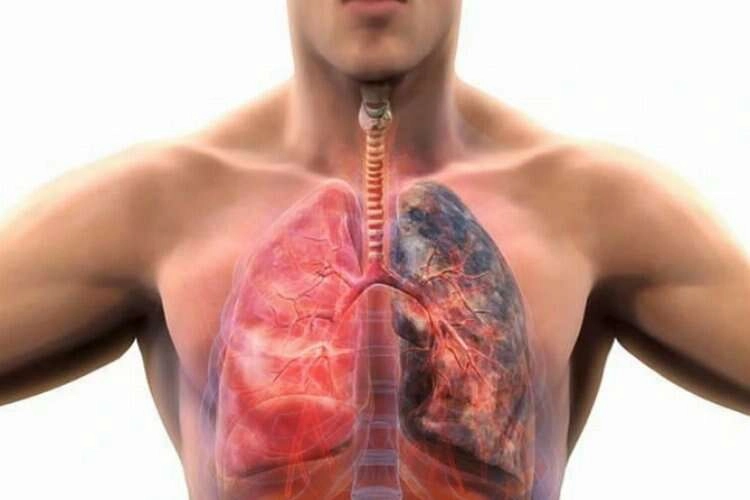

Nefes borularını daraltarak akciğerlerden solunum havasının dışarıya çıkışını yavaşlatan bir hastalık olan KOAH, efor sırasında yeterli solunum yapılamadığı için nefes darlığı şikayetiyle başlıyor. Nefes darlığına neden olan kronik ve ilerleyici bir hastalık olan KOAH'da nefes darlığına sıklıkla öksürük ve balgam çıkarma eşlik ediyor.

Sigara dumanı ve diğer zararlı gaz ile tozlara yıllarca maruz kalınmasıyla, nefes boruları ve hava keseciklerinin (alveollerin) yapılarının bozulduğunu belirten Prof. Dr. Mecit Süerdem, “Nefes borularının yapısında bozulma ve daralmaya bağlı oluşan hastalığa ‘kronik tıkayıcı bronşit', çok küçük nefes boruları ile hava keseciklerinin harabiyeti ve parçalanması ise ‘amfizem' olarak isimlendirildiğini belirtti.

"KOAH bu iki hastalığı kapsayan bir terimdir ve genellikle bu iki hastalık bir arada bulunur” diyen Prof. Dr. Süerdem, sigara içenlerin en az yüzde 25'inde KOAH'ın geliştiğinin söyledi.